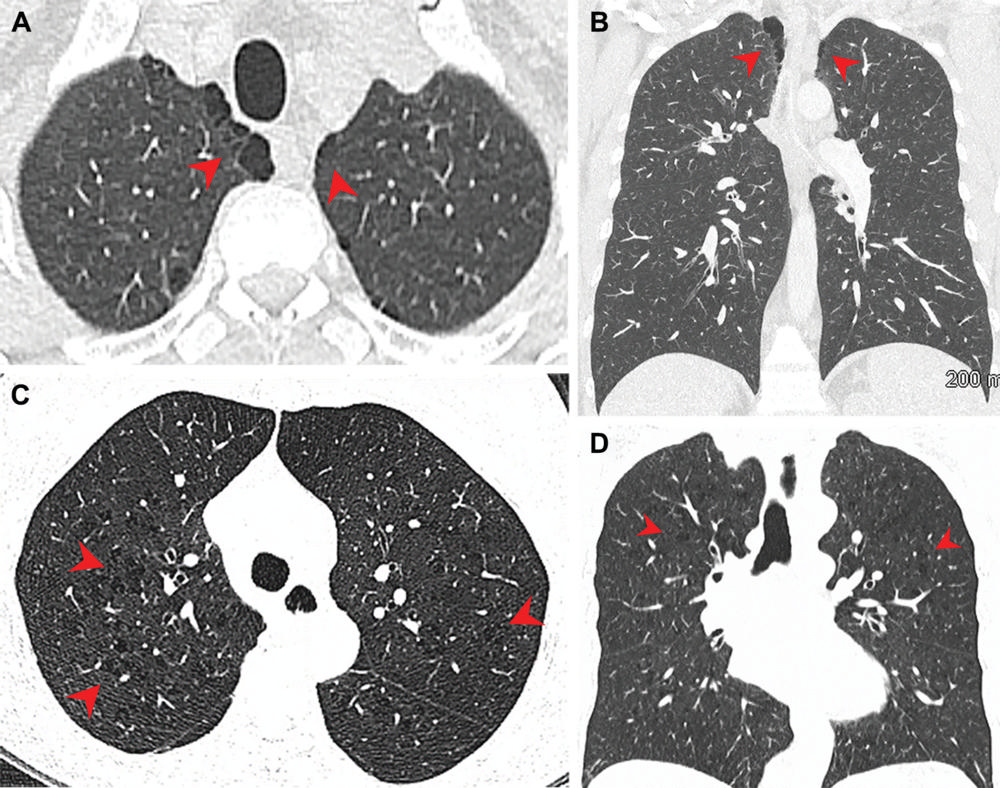

Figure 3. Pulmonary emphysema in marijuana and tobacco smokers. CT images in a male marijuana smoker show paraseptal emphysema in bilateral upper lobes. CT images in a female tobacco smoker with centrilobular emphysema. (Courtesy of Radiology)